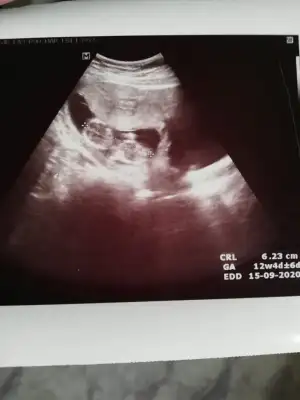

tmm ben ayrıntılı ultrasonda netleşince size dönüş yapacağımBencede kız 2 defa kız demiş aynı drusg de nub da kız gibi geri dönüş yaparsanız sevinirim

M mely15 bi bakarmısın canım ben tahmin ettim arkadaşa sen ne diyorsun 12+4 usgKızlar kızlarvideodan ekran görüntüsü aldığım 2 fotoğrafta nub birinde paralel birinde dik duruyor hareket ettiği sırada değişiyor olabilir mi

Kız gibi gibi diyorum net değil usg başka varsa paylaşın emin olamadım12+4 günlük yorumlayabilir misiniz![]()

Sanki kız gibi ama emin değilim nubu karanlık kalmış 12 yada 13 haftada paylaşın emin olmak istiyorum![]()

Maalesef başka ultroson fotoğrafı yok. Kontrole gidersem atarım. TeşekkürlerKız gibi gibi diyorum net değil usg başka varsa paylaşın emin olamadım![]()

Kız gibiIkra meyra tekrar usg paylaşın demiştiniz sat a göre 12+1 ultrasona göre 12+6 çıktık ❤Pazartesi tekrar gideceğim ama bunu da atmak istedim belki bir tahmin olur